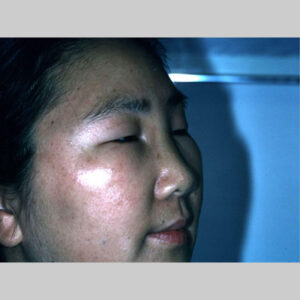

Angioedema is the swelling of deep dermis, subcutaneous or submucosal tissue due to vascular leakage.1 It was first described in 1586.2 Other terms, such as giant urticaria,3 Quincke edema,4 and angioneurotic edema,5 have also been used in the past to describe this condition. Clinically, angioedema is usually nonpitting and nonpruritic. The area of involvement is often skin-colored or slightly erythematous. Depending on the area of swelling, pain can be absent or mild, as in most peripheral or facial swelling, or can be very severe, as in gastrointestinal angioedema. Laryngeal swelling is life-threatening. It should be treated as a medical emergency.

Patients usually describe swelling of the face (eg, eyelids, lips), tongue, hands, and feet. It can be acute or chronic, and each episode of angioedema may last a few hours to a few days. A local burning sensation and pain can be observed without pronounced itchiness or local erythema. Abdominal pain can sometimes be the only presenting symptom of angioedema. Throat tightness, voice changes, and trouble breathing may indicate airway involvement.

For skin involvement, examination can easily identify areas of swelling with or without erythematous skin, often with ill-defined margins. Some cases of angioedema occur in patients with urticaria.